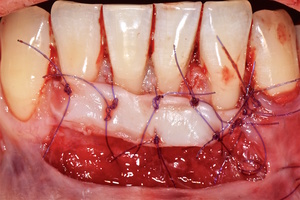

1. Генерализованные рецессии в области нижней челюсти оперировались в один этап все 12 зубов, фронтальный участок с аутотрансплантатом от 3.2 до 4.2 зубов. А дистальные участки от 3.6 до 3.3 и от 4.6 до 4.3 зубов с использованием пластического материала ТМО (dura mater) (рис. 4а-з).

1. Подготовка принимающего ложа. Включает в себя формирование полнослойно-расщепленного слизисто-надкостничного лоскута (полнослойного в области зенитов рецессий, расщепленного билатерально области рецессии десны), рассечение и отслаивание слизисто-мышечных волокон вестибулярно ниже мукогингивальной границы, деэпителизация межзубных сосочков.

2. Обработка поверхностей корней зубов. Включает ультразвуковую обработку скейлером для очищения от минерализованных зубных отложений и мягкого зубного налета, экспозицию геля ЭДТА 17% в течение двух минут, механическое удаление слоя бесклеточного цемента импрегнированного микроорганизмами зоноспецифическими кюретами, полировку пародонтологическими борами («фасолька» и «обратный треугольник»).

3. Получение аутотрансплантата: начинается с определения толщины донорской зоны и замеров размера будущего трансплантата. Зона забора от второго премоляра до третьего моляра верхней челюсти. Глубина погружения брюшка скальпеля 2 мм, далее трансплантат оптимизируют — деэпителизируют по периметру.

4. Затем проводиться позиционирование аутотрансплантата в области рецессий и принимающего ложа двумя-тремя узловыми швами; после аутотрансплантат стабилизируют прижимающими двумя-четырьмя матрасными крестообразными швами, что позволит плотно прижать аутотрансплантат и избежать образования «мертвых» зон для питания аутотрансплантата.

4. Фиксация пластического материала ТМО (dura mater) к поверхности корней зубов в области зоны создания необходимого объема прикрепленной десны.

5. Закрытие пластического материала слизисто-надкостничным лоскутом со смещением в корональном направлении, и фиксация слизисто-надкостничного лоскута швами; дополнительная фиксация зоны перемещенных и в будущем созданных мягких тканей десны в зоне рецессии десны для стабилизации результата операции.